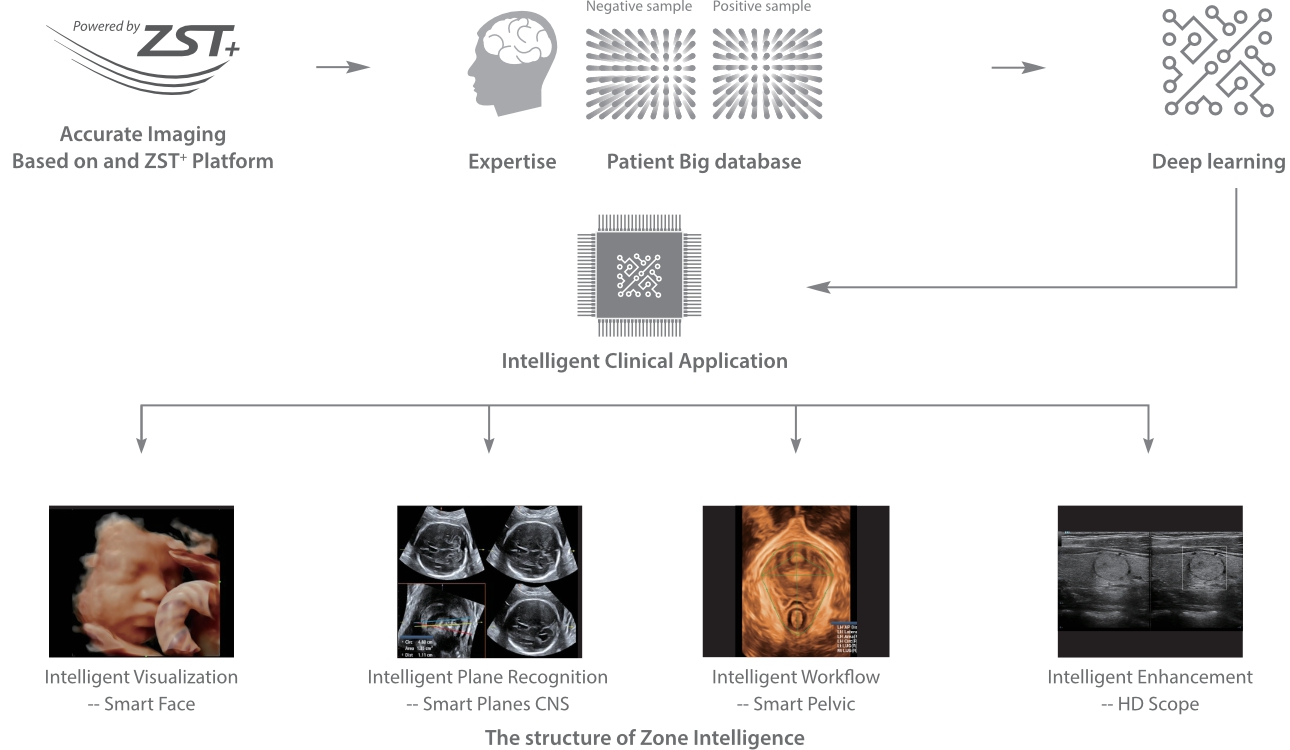

Mindray, ?irketin kuruldu?u gĂŒnden bu yana sĂŒrekli olarak tan?sal do?rulu?u iyile?tirmeye ?al??maktad?r. Devrim niteli?indeki ZONE Sonography? Teknolojisi ile desteklenen Resona 7ânin yeni ZST+ platformu, b?lge g?rĂŒntĂŒsĂŒ alma ve kanal veri i?leme ?zellikleri ile ultrason g?rĂŒntĂŒsĂŒ kalitesini daha ĂŒst bir dĂŒzeye ??kar?yor.

Resona 7, ĂŒstĂŒn dĂŒzeyde g?rĂŒntĂŒ kalitesine ek olarak, vaskĂŒler hemodinamik de?erlendirmesi i?in devrim niteli?indeki V Ak??? ile fetĂŒs CNS tan?lamas? i?in 3 boyutlu veri kĂŒmesinden dĂŒzlem g?rĂŒntĂŒsĂŒ alma konusunda en iyi birime sahip oldu?undan, klinik ara?t?rma yeterliklerini de art?rmaktad?r. En sezgisel, harekete dayal? ?oklu dokunmatik i?letim ile tĂŒm temel klinik ?zellikleri bir araya getiren Resona 7, ultrason yenili?i konusunda ger?ek anlamda yeni dalgalara ?ncĂŒlĂŒk ediyor.